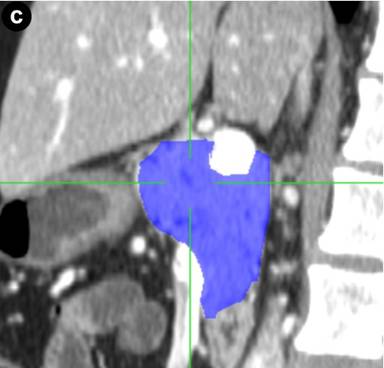

Preoperative computed tomography or magnetic resonance imaging were analyzed by the same radiologist who was blinded to the postoperative course. The volume of the pancreatic remnant was measured using a Voxar® 3D workstation (Barco NV, Kortrijk, Belgium) with 3D segmentation and volume calculation (Figures 1 and 2). The length and width of the resection plane were measured. The caliber of the main pancreatic duct was measured in the resection plane and in the head of the pancreas, as was the distance of the resection margin from the lesion.

Figure 2. Computed tomography of the pancreas showing 3D segmentation and volume calculation of the pancreatic remnant (in blue) in transverse (a.), coronal (b.), and sagittal (c.) images. |